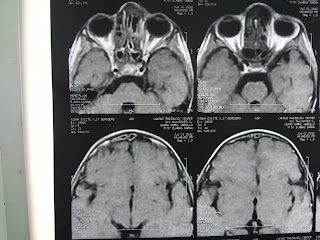

male patient 45 years old has bilateral neck mass in relation to carotid arteries

scanned with ct carotid angiograghy which detect bilateral hypervascular neck swelling

which excised on one side only and send for HPE and reveal a glomus vagale tumor.